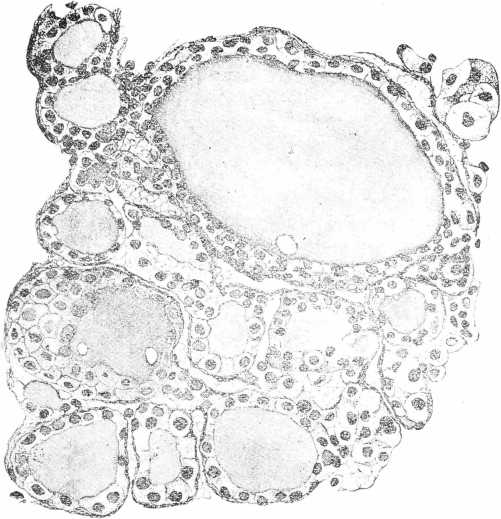

Наибольшія измѣненія въ щитовидной железѣ наступали подъ вліяніемъ тиреолитической сыворотки и адреналина, при чемъ подъ вліяніемъ этихъ агентовъ они развивались не съ одинаковой быстротой и не съ одной и той же интенсивностью. Скорѣе всего измѣненія щитовидной железы обнаруживались въ опытахъ съ тиреолитической сывороткой. Въ одномъ рядѣ случаевъ ихъ можно было наблюдать уже спустя 1 часъ послѣ впрыскиванія въ v. jugubaris 30 куб. цен. сыворотки. Въ это время удавалось констатировать умѣренное расширеніе сосудовъ, появленіе значительнаго количества большихъ эпителіальныхъ клѣтокъ въ стѣвкахъ фолликуловъ съ свѣтлой протоплазмой. Еще болѣе рѣзкія измѣненія приходилось встрѣчать при изслѣдованіи железы черезъ 6—24 часа (см. табл. II. рис. 3) послѣ впрыскиванія тиреолитической сыворотки. Протоплазма железистыхъ клѣтокъ представляется крайне набухшей, разрыхленной и пронизанной вакуолями, нѣкоторыя клѣтки превращались прямо въ сѣтку, въ которой виднѣлись довольно хорошо сохранившіяся ядра. Количество коллоидныхъ клѣтокъ въ одномъ рядѣ случаевъ казалось увеличеннымъ въ числѣ, въ другомъ оставалось въ предѣлахъ нормы. Величина фолликуловъ и степень растяженія ихъ коллоидомъ непостоянно, также постоянно измѣненіе калибра кровеносныхъ сосудовъ, непредставляющихся то болѣе, то менѣе широкими. Дальнѣйшія измѣненія щитовидной железы, насколько позволяютъ судить наши препараты, сводятся къ постепенному возвращенію органа къ нормальному состоянію. Протоплазма славныхъ железистыхъ клѣтокъ принимаетъ вновь зернистый видъ. Вакуоли занимаютъ только небольшую частъ клѣтки. Этотъ процессъ возстановленія обычной структуры клѣточнаго тѣла происходитъ въ однихъ случаяхъ довольно быстро, такъ что по истеченіи уже 24 часовъ щитовидной железѣ наблюдается картина, почти соотвѣт ствующая уже той, которая встрѣчалась у нормальныхъ животныхъ. (См. табл. III. рис. 5). Въ другихъ случаяхъ тотъ же процессъ идетъ гораздо медленнѣе и по истеченіи 48 часовъ на препаратахъ изъ щитовидной железы можно было встрѣтить еще глубокія измѣненія строенія въ фолликулахъ съ преобладаніемъ сильно разбухшихъ, безцвѣтныхъ, лишенныхъ нормальной зернистости протоплазмы клѣтокъ, ядра которыхъ частью были смѣщены и окрашивались диффузно. (См. табл. II, рис. 4).

Рис. 2. Фолликулъ щитовидной железы кошки въ состояніи секреціи, подъ вліяніемъ адреналина. Фиксація въ жидкости Bouimа. Окраска по способу Jоrіs’a. Увеличеніе: Zens. Ocular 4. Object, homog. immers.